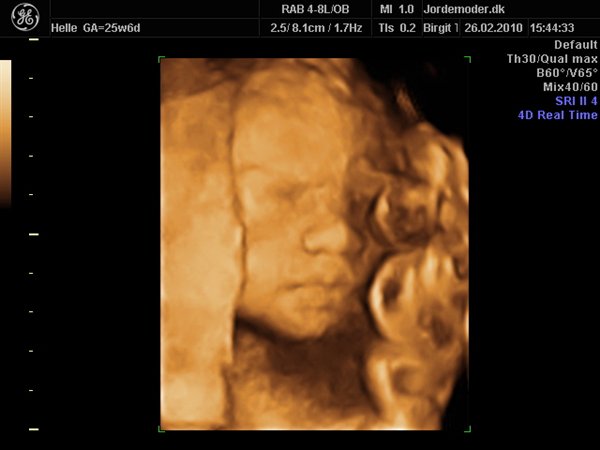

Og hun er en hun. Helt sikkert. Så det selv tydeligt og jordemoderen var også helt sikker.

Det gik fint i starten. Hun smilede og lavede grimasser og lå helt perfekt. Så vi fik en masse fine billeder ret hurtigt. Men pludselig gad hun ikke mere. Overhovedet! Jeg var oppe at hoppe, gå på trapper og drikke isvand. Men nej, prinsessen skulle have sin skønhedssøvn. Lige midt i scanningen...

Her er hun: